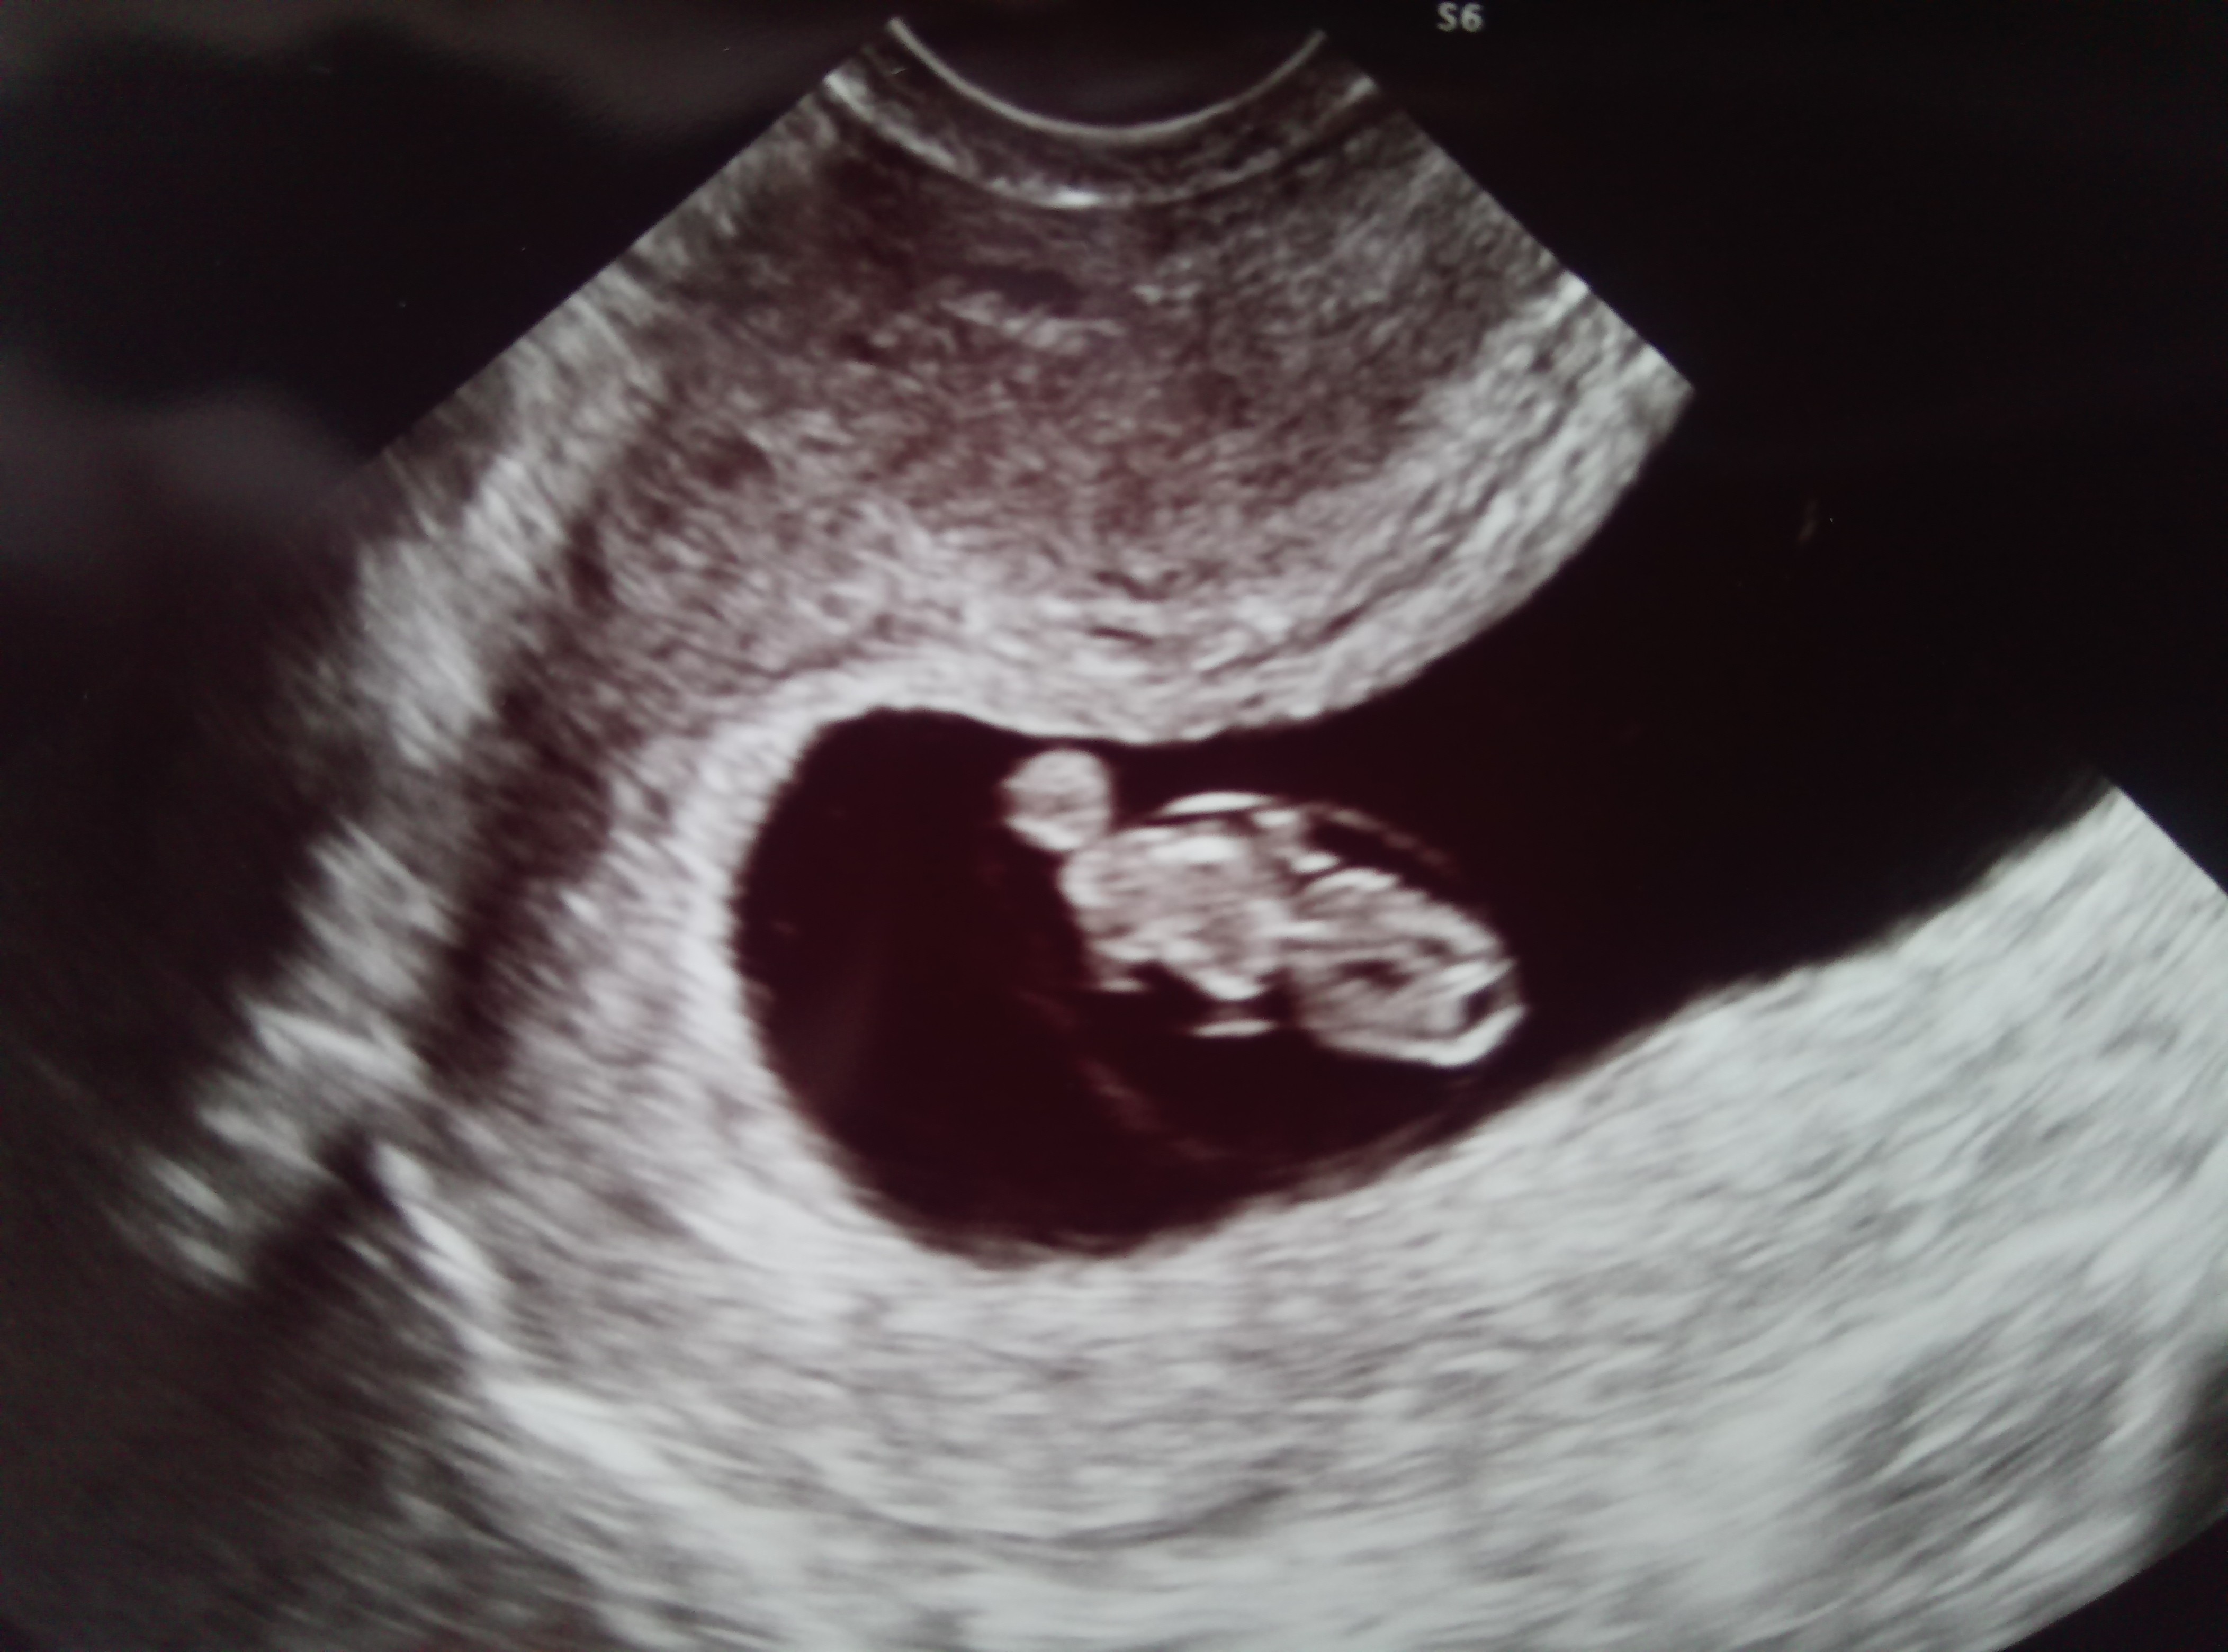

Ja znów po wizyciewidziałam piękne 2 cm dziecko

z USG 8+2 dni

serduszko pięknie pracuje. Jak dotąd wszystko dobrze. Pozdrawiam Was